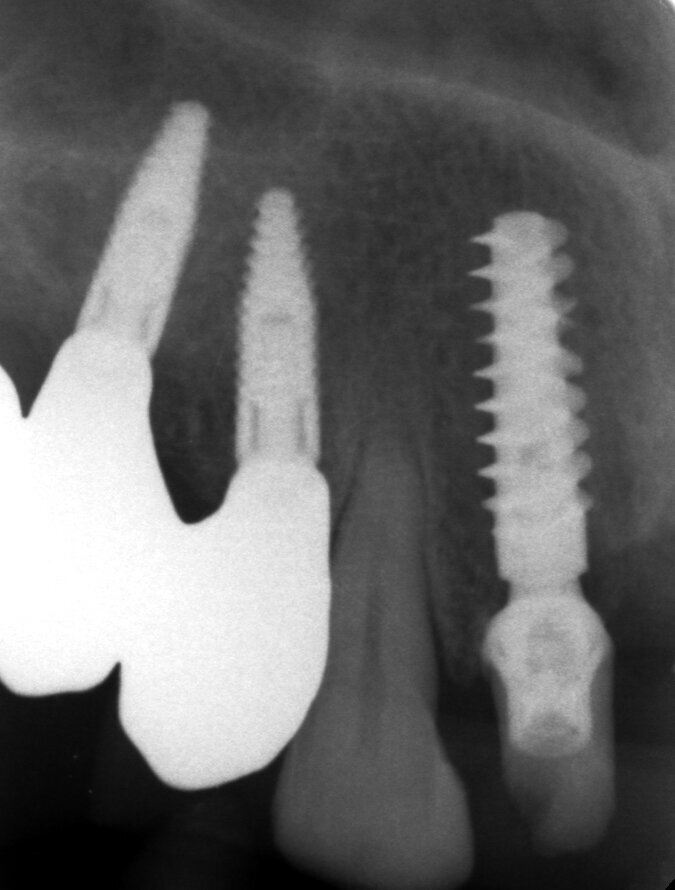

Il piano di trattamento prevede l’estrazione degli elementi dentali, l’inserimento di due impianti e la realizzazione di una protesi fissa di quattro elementi. Il problema da gestire è quello della fase provvisoria. Non è ipotizzabile una protesi mobile e quindi programmiamo di inserire subito dopo l’intervento un provvisorio immediato. Questo ci consente di condizionare da subito i tessuti periimplantari e anche le zone dei ponti. Si rileva un’impronta digitale (Figg. 5, 6), e la programmazione degli impianti viene effettuata con un software di chirurgia guidata (Fig. 7) e la posizione degli impianti nello spazio biologico e nello spazio protesico viene fatta sulla base di una ceratura diagnostica (Figg. 8, 9). Inseriamo gli impianti virtuali nell’osso disponibile (Figg. 10-13) e in relazione all’aspetto protesico correggiamo l’asse di inclinazione degli impianti con componenti secondarie angolate a 17° (Figg. 14, 15). Questo ci consentirà di realizzare una protesi avvitata con i fori situati nella zona palatale.

Fig. 10 - Posizionamento virtuale dell’impianto 1.2.

Fig. 11 - Posizionamento virtuale dell’impianto 2.2.

Fig. 12 - Cross impianto 1.2.

Fig. 13 - Cross impianto 2.2.

Il nostro obiettivo è quello di riuscire a dare alla paziente un provvisorio immediato nell’arco di due ore. Questo diventa possibile perché abbiamo utilizzato un flusso digitale fin dall’inizio. In laboratorio vengono realizzate la dima chirurgica (Figg. 16, 17), la dima protesica (Fig. 18) e anche il provvisorio (Figg. 19-21) che contiene delle alette di riposizionamento. Il tutto gestito con modelli digitali sui quali saremo in grado di funzionalizzare il provvisorio post-chirurgico (tecnica DIL). In un caso come questo se utilizziamo un flusso digitale possiamo evitare subito dopo la chirurgia di rilevare un’impronta degli impianti inseriti. Infatti, utilizziamo una dima chirurgica che ci faciliterà le fasi di intervento. La dima ci consentirà di non fare lembi e nessuna incisione di rilascio (Fig. 22), dopo aver inserito gli impianti (BLX Straumann) (Figg. 23-31) e aver controllato il loro alloggiamento, inseriamo sugli stessi dei transfert da impronta (Fig. 32).